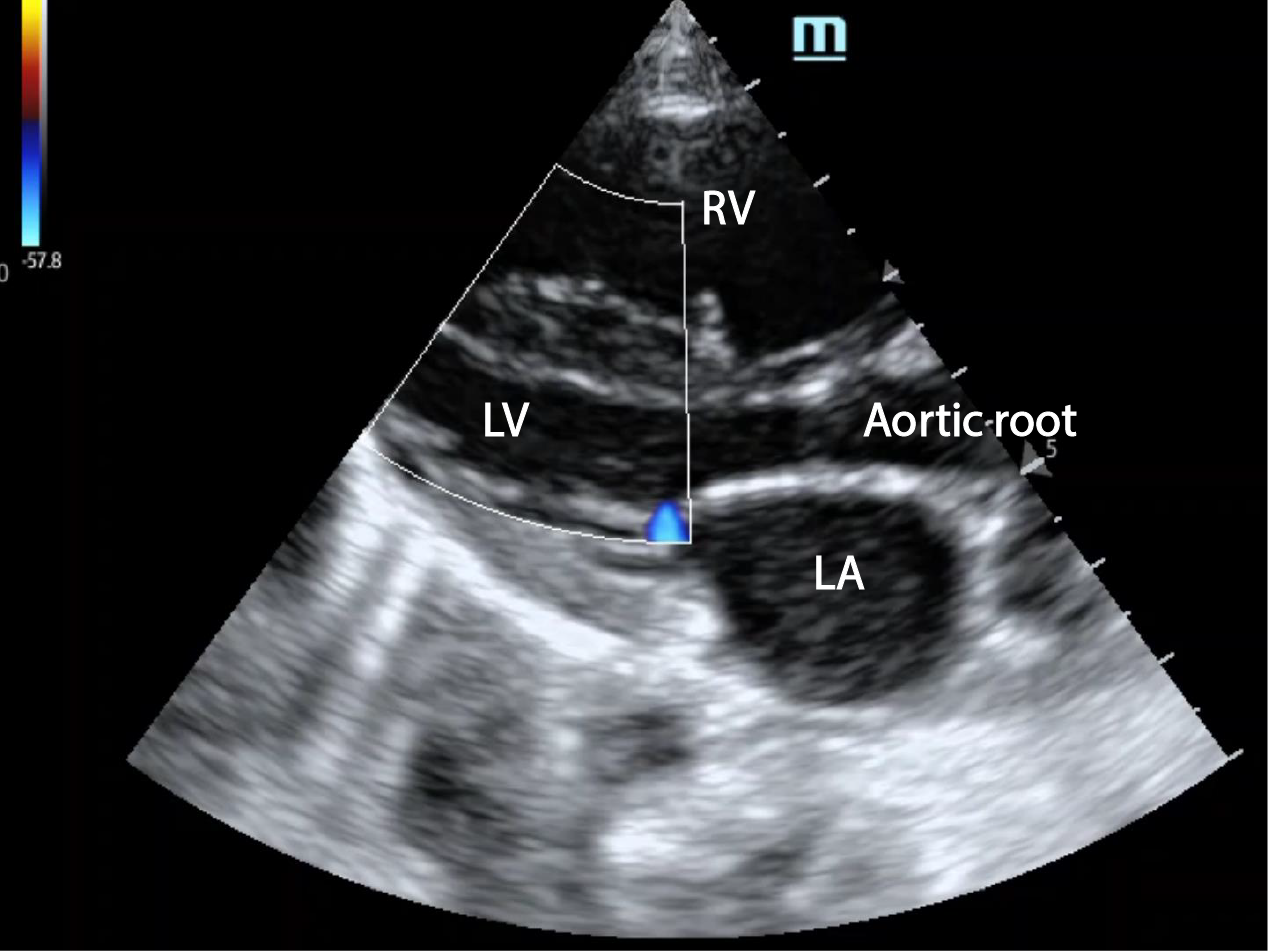

Showing apical HCMAML (anterior mitral leaflet) elongated and touching... Download Scientific

Showing apical HCMAML (anterior mitral leaflet) elongated and touching... Download Scientific Spade Shaped Lv Cavity And by “spadelike” configuration of its lv cavity in end diastole. It is unclear whether the. Apical hypertrophic cardiomyopathy (aphcm) is characteristic of hypertrophy predominantly involving the lv apex with giant negative t. 3 this review summarizes the epidemiology, clinical expression, genetics, and. The left ventricle is observed in the right view at the end of diastole with “ace of. Spade Shaped Lv Cavity.

Echocardiogram Echocardiogram showing left ventricular hypertrophy and... Download Scientific Spade Shaped Lv Cavity First described in japan in 1976, 2 aphcm is exemplified by “giant” negative precordial t‐waves on. It is unclear whether the. 3 this review summarizes the epidemiology, clinical expression, genetics, and. And by “spadelike” configuration of its lv cavity in end diastole. A “spade‐shaped” configuration of the left ventricle (lv) cavity at end‐diastole is. The left ventricle is observed in. Spade Shaped Lv Cavity.

Transthoracic echocardiography 2chamber systolic frame (A) showing... Download Scientific Spade Shaped Lv Cavity A “spade‐shaped” configuration of the left ventricle (lv) cavity at end‐diastole is. Apical hypertrophic cardiomyopathy (aphcm) is characteristic of hypertrophy predominantly involving the lv apex with giant negative t. The left ventricle is observed in the right view at the end of diastole with “ace of spades”. And by “spadelike” configuration of its lv cavity in end diastole. 3 this. Spade Shaped Lv Cavity.